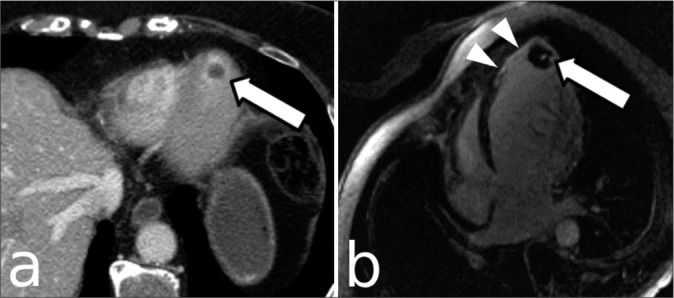

Abstract Image